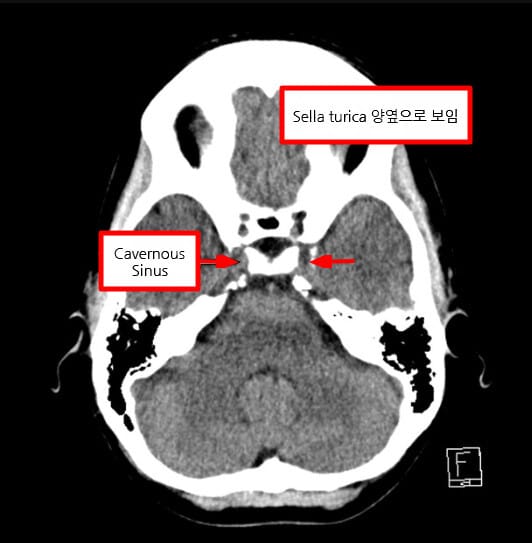

Cavernous Sinus

Cavernous sinus는 접형골(sphenoid bone) 옆쪽에 위치한 정맥혈이 흐르는 공간으로, Dura mater 사이에 존재하는 큰 정맥굴입니다.

- Axial view에서 뇌하수체(sella turcica) 양 옆으로 대칭적으로 보입니다